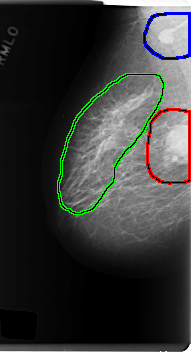

FILE: C_0189_1.RIGHT_CC.OVERLAY

TOTAL_ABNORMALITIES 2

ABNORMALITY 1

LESION_TYPE CALCIFICATION TYPE PLEOMORPHIC DISTRIBUTION CLUSTERED

LESION_TYPE MASS SHAPE ROUND MARGINS SPICULATED

ASSESSMENT 5

SUBTLETY 5

PATHOLOGY MALIGNANT

TOTAL_OUTLINES 1

ABNORMALITY 2

LESION_TYPE CALCIFICATION TYPE PLEOMORPHIC DISTRIBUTION REGIONAL

BOUNDARY